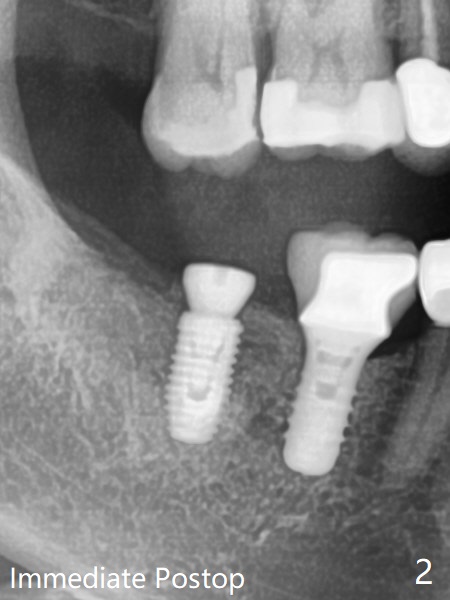

61岁女右下7导板钻洞,第一个钻头(环形钻)就有困难入位,部分磨去对合7近中腭侧牙尖(图一:*),钻头入位就好多了(图二:^,对比)。钻洞时发现骨质密度中等,所以最后钻头直径4.5毫米。不过无法用手植牙工具旋入植体,使用5.0毫米功螺纹钻头后,手工具就好用了,植体植入一定深度,扳手有空间插入,最后扭力30Ncm。第二个问题,当按照设计深度植入植体,用探针检查颊侧好像没有骨壁;加深大约0.5毫米(仿佛没有取到目的,颊侧骨板不明显)后,使用6毫米profile钻头,插入5.5x3毫米愈合基台(图二,三),在基台和颊侧牙龈之间植入异体骨粉,但愿帮助颊侧骨板再生。术后一周内敷料脱落,颊侧伤口愈合,好像骨粉没有流失。术后2.5月愈合基台脱落,换至小号基台(4向毫米),仍旧疼痛,休息2分钟,手拧紧,拍摄根尖片,仿佛就位(图四)。准备一周后调换稍微大,例如,4.8毫米基台。术后3.5个月,5.2毫米基台好像没有就位(图五:<),可能与远中牙槽嵴接触(*)。小一号基台仿佛就位(图六),与远中牙槽嵴无接触。术后4个月粘固后基台螺丝拧紧30Ncm。术后8个月,也就是粘固后4个月,牙槽嵴似乎试图覆盖植体平台(图七:箭头)。